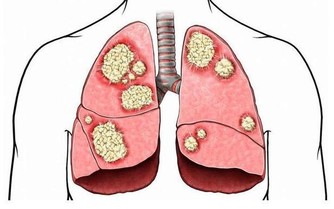

在目前的中國,看病真的好貴,若不幸得了癌症,簡直就是一病回到解放前。更糟糕的是,查出的癌症大多是晚期,有錢也未必治得好,腸癌就是其中典型的例子。

數據顯示腸癌現狀在我國,每年新增結直腸癌竟達40萬例,平均每5min就有1人死於腸癌。

早期腸癌的臨床診斷率僅為11%-15%,治愈率高,術後5年生存率可達95%;而超過80%的患者確診腸癌時,

已發展至中晚期,治愈效果並不理想,5年生存率只有5%左右。